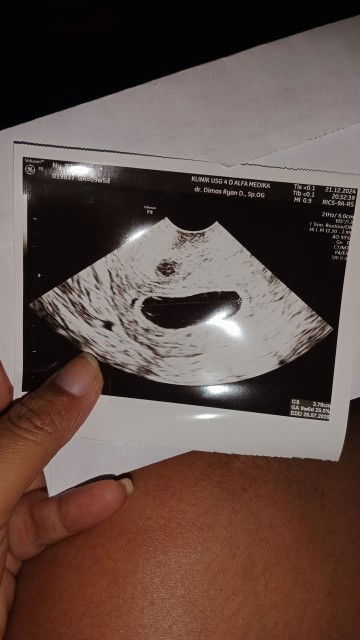

hpht 14 okt, siklus haid 35 hari usia usg dan hpht sama 9week5day tgl 21 des, tetapi hanya kantung saja, suspect BO tapi disuruh kembali usg 3 minggu lagi utk observasi apakah janin muncul atau tidak tapi sebelumnya saya usg di bidan masih 6 week6day pas tanggal 11 des apa ada yg pernah mengalami bun? sharing dongg #Sharing_dong_Bund #SeriusTanya